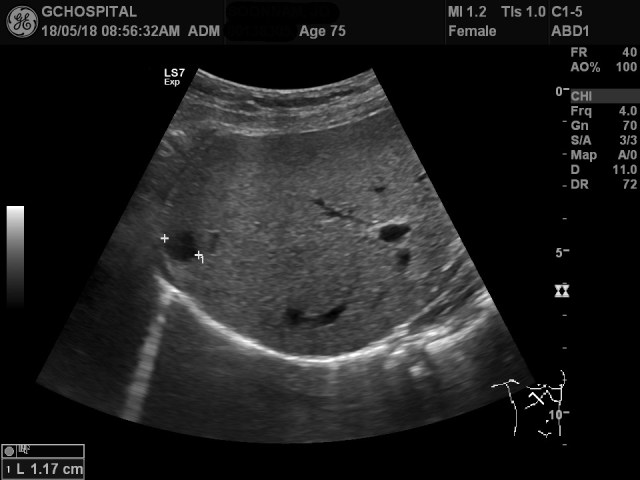

75세 여자 환자로 건강검진을 위해 초음파를 시행 중, 간의 지붕쪽에 1센티미터 크기의 단순낭종을 발견했습니다.

이 단순낭종을 발견한 당시 환자는 좌측 측와위자세를 취하고 있었습니다.